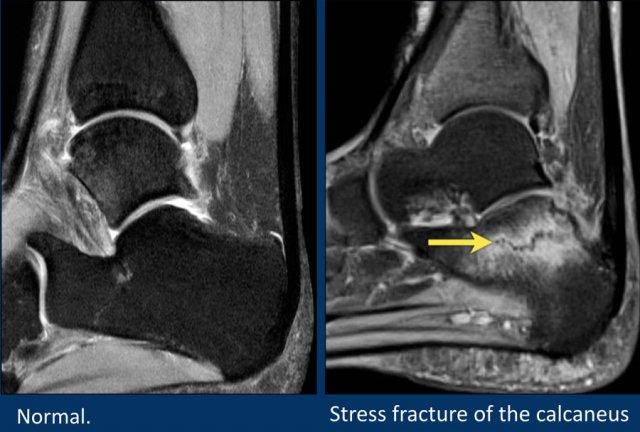

Gãy xương do stress ở xương gót (calcaneus) là một nguyên nhân gây đau gót chân thường bị bỏ sót.

Bệnh nhân này có phù nề ở xương gót do gãy xương stress.

Tổn thương này thường là hậu quả của việc sử dụng quá mức, đặc biệt ở những người chạy bộ.

Khi không thấy rõ đường gãy trên chuỗi xung T2W fatsat, hãy xem xét các chuỗi xung T2W không fatsat hoặc chuỗi xung T1W để tìm đường gãy giảm tín hiệu.

Đôi khi đường gãy không được nhìn thấy trên MRI.

Trong những trường hợp đó, có thể cân nhắc chụp CT vì phương pháp này có thể nhạy hơn.